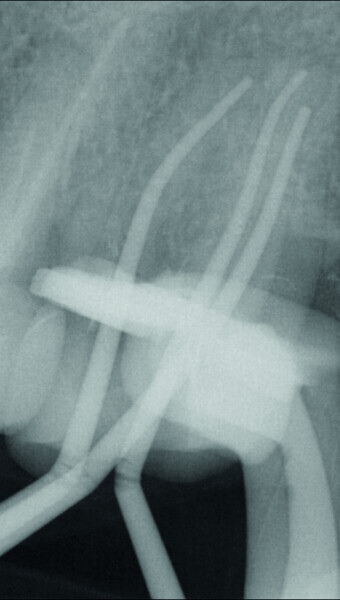

Fig. 9 : Maîtres cônes mis en place dans le canal.

Fig. 10 : Radiographie des maîtres cônes pour confirmer la longueur de travail définie.